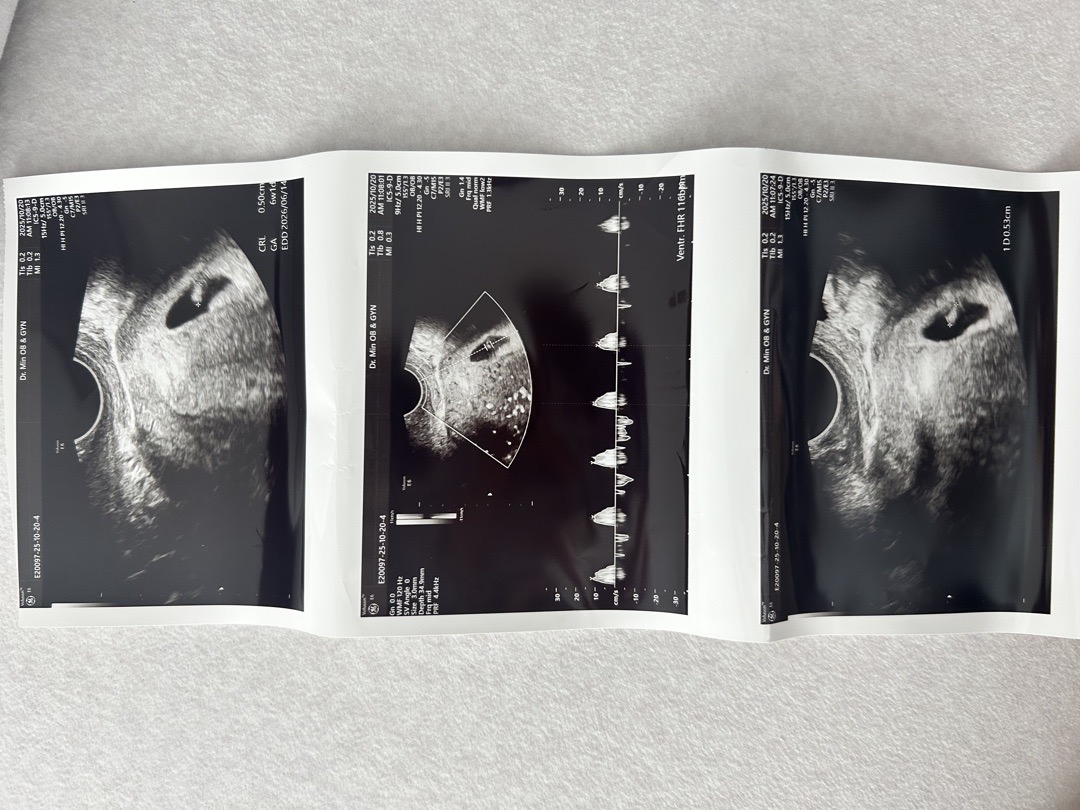

아기집이 너무 한쪽으로 쏠려있나 싶어서요ㅠ_ㅠ 오늘 5주 5일차이고 고맙게도 심장소리 들려줘서 듣고 왔습니다❤️ 0.5cm라고 하네요ㅎㅎ 아기집 커지면서 위치도 조금씩 달라지는 거겠죠~?